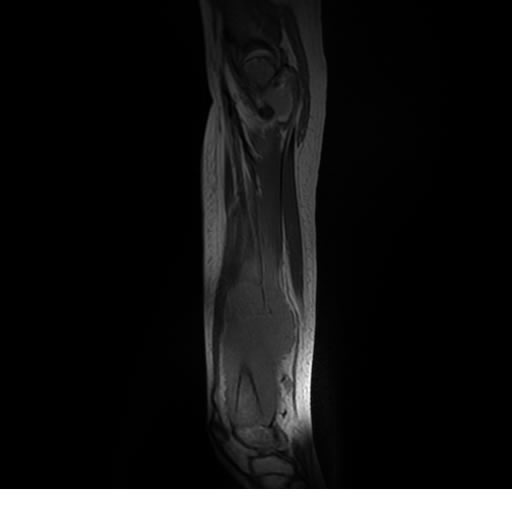

Se realiza estudio de MRI de muslo izquierdo en diferentes planos, con secuencias de Spin Echo, GRE; ponderadas a T1 y a T2, se utilizan pulsos de saturación de grasa y se administra medio de contraste IV a base de Gadolinio en base al peso del paciente.

La diáfisis femoral izquierda muestra reacción perióstica importante, se extiende desde el cuello del fémur, invade trocánteres, diáfisis femoral, medial y distal, es compatible con un proceso infeccioso óseo, el complejo muscular del muslo se ve edematizado.

Hallazgos en Resonancia Magnética (RM)

La resonancia es la modalidad de elección para valorar la extensión intramedular y la infiltración en tejidos blandos, brindando una imagen más detallada del compromiso tumoral. Los hallazgos característicos incluyen:

Lesión de señal heterogénea en secuencias T1 (hipointensa) y T2/STIR (hiperintensa), que refleja necrosis, hemorragia y contenido celular diverso.

Realce intenso y heterogéneo tras la administración de contraste (gadolino), lo que indica vascularización tumoral.

Compromiso de la médula ósea adyacente y de estructuras vecinas, como músculos y neurovasculatura.

Posible presencia de edema óseo y necrosis central.